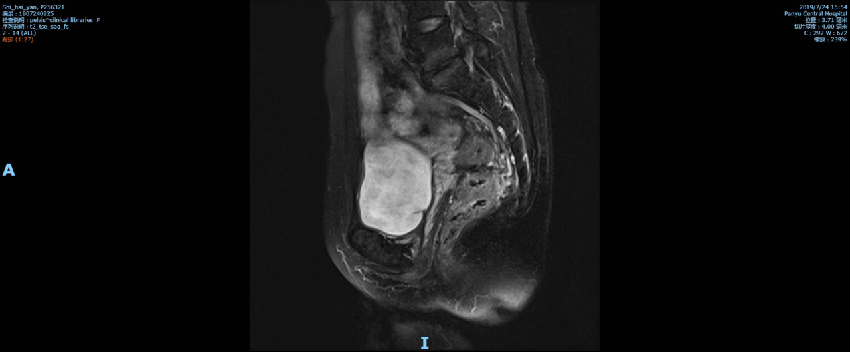

盆腔MR示:直肠全段管壁不均匀增厚,以中段较明显,最厚处约15mm,部分肠腔内见软组织肿块影突起,上下累及范围约70mm,距肛门距离约50mm,结肠浆膜面稍毛糙,局部与前筋膜分界不清,周围脂肪间隙部分略欠清;符合直肠癌改变,考虑累及浆膜面,不除外直肠前筋膜受累;

影像学检查资料: